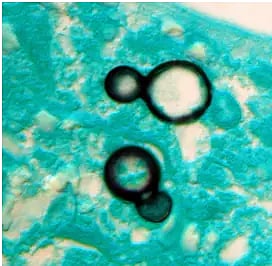

Aspergillus, Candida, Nakaseomyces glabratus, and Trichophyton indotineae are the major fungicide resistant infections. These can have devastating health impacts on the elderly and people with weak immune systems.